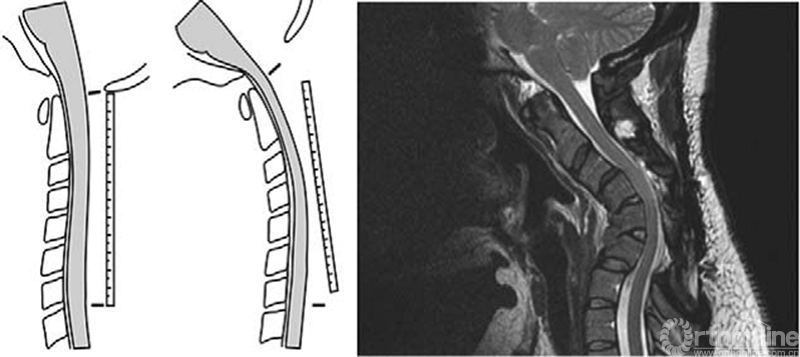

任何原因所致的颈椎后方组织退化及退行性改变,可导致椎间盘/椎体高度丢失,颈椎轴向负荷前移。随着SVA的增加,颈椎进行性后凸造成脊髓在后纵韧带上拉伸和挤压,常伴随着脊髓的血供减少,由于齿状韧带的约束作用使得脊髓垂直张力增加。与成人脊髓栓系综合征一样,脊髓拉伸可能导致脊髓病,必须手术处理。

脊髓与矢状面平衡关系。脊髓覆盖在后纵韧带上(左);MRI(右)